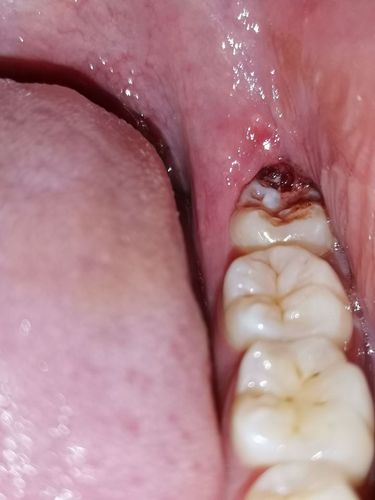

智齿包肉里怎么办图片

智齿包肉里怎么办图片,智齿包在肉里面图片

智齿牙后面长了一小块肉,这是怎么回事啊?

大夫说智齿位置长的正着呢,不用拔了,等消炎了把牙齿上盖的肉割了应该

智齿发炎肿图片智齿冠周炎脓肿切开图

智齿包在肉里面图片

肉包智齿图片

智齿半包在肉里面图片

智齿后面的肉肿了图片

牙齿被肉包住了图片

尽头牙长肉包裹图片

智齿长出一半被肉包着

智齿露一半包一半图